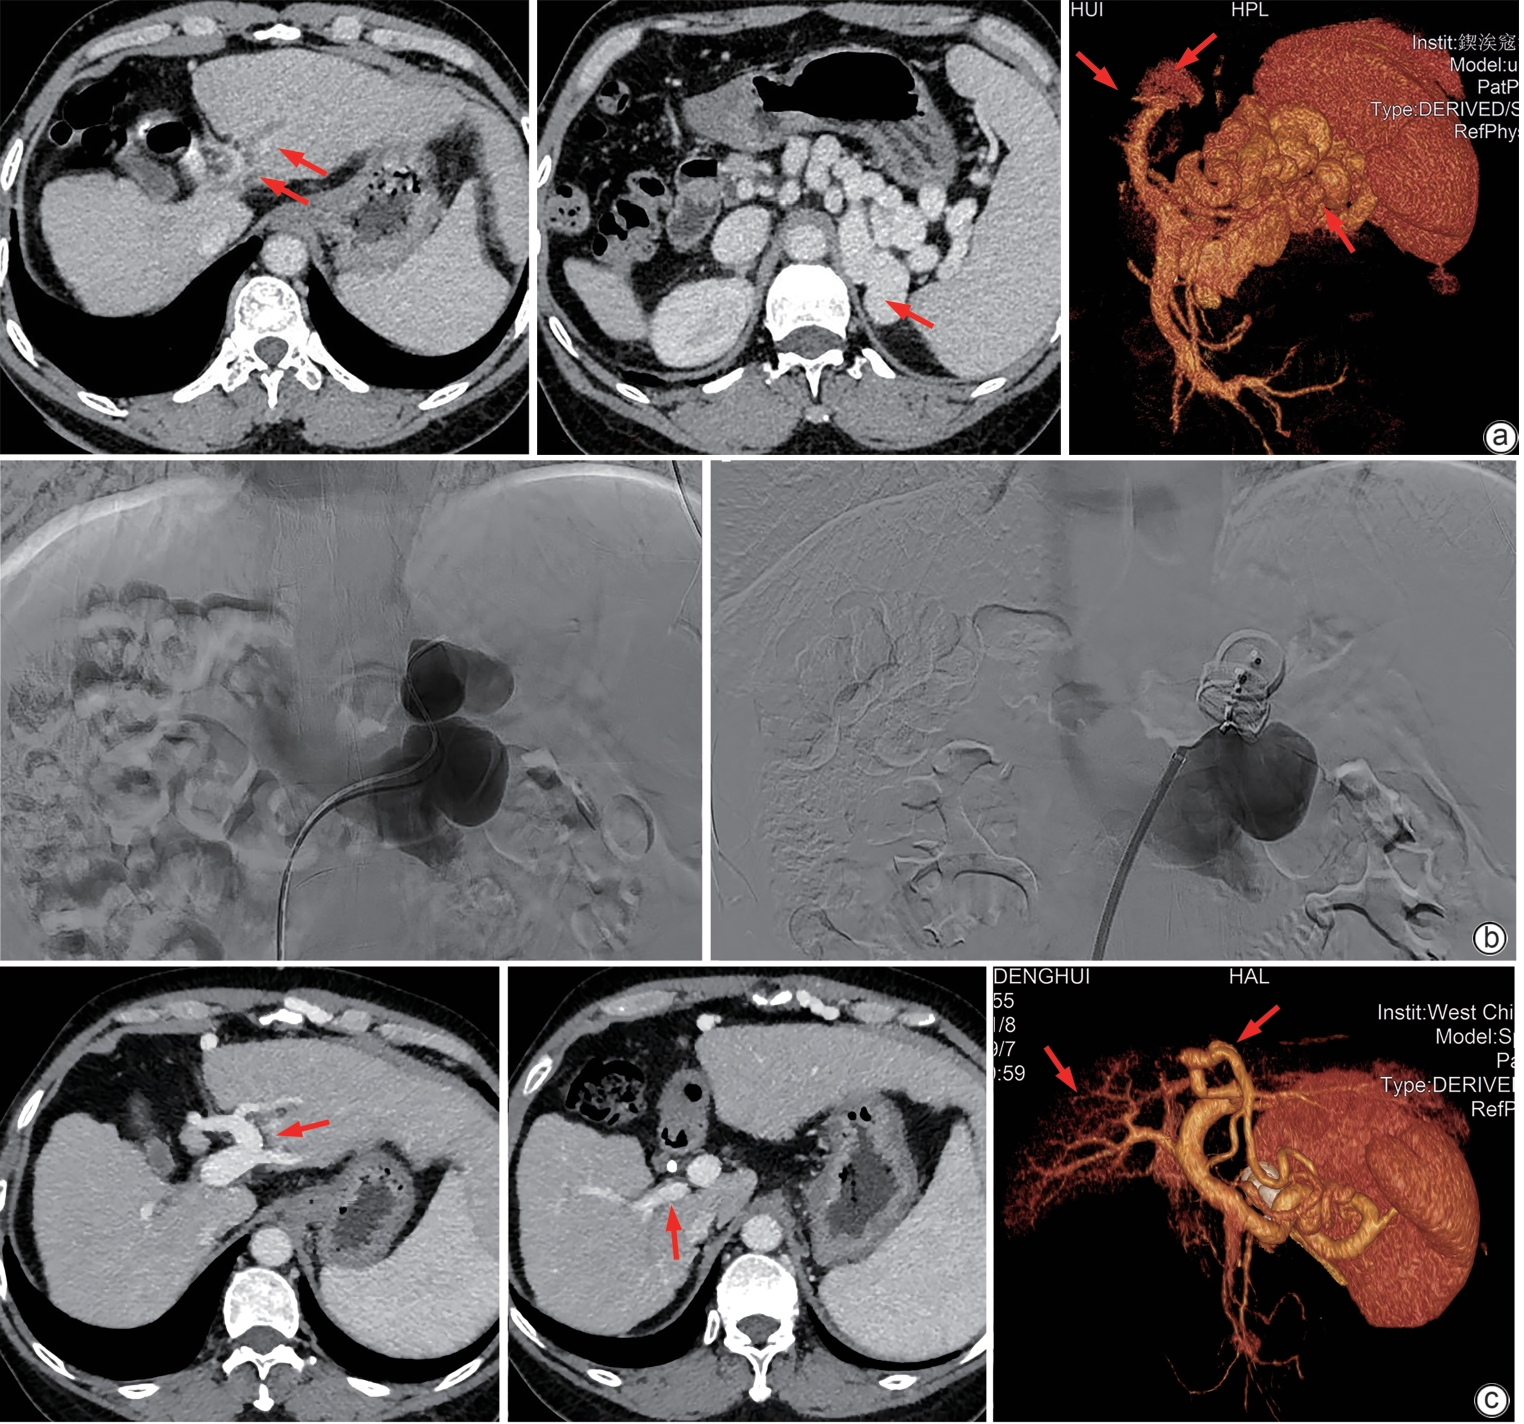

摘要: 门静脉血栓是肝硬化患者常见且严重的并发症,门静脉血流动力学的改变与门静脉血栓的发生密切相关。合并巨大的自发性脾肾分流时门静脉灌注减少、血流速度减慢,极有可能削弱门静脉血栓的抗凝效果。本文将报道1例通过栓塞自发性脾肾分流道联合抗凝治疗策略,实现了门静脉的完全再通,然而,仍需高质量的临床研究进一步验证和支持这一策略的有效性。Abstract: Portal vein thrombosis (PVT) is a common and severe complication in patients with liver cirrhosis, and alterations in portal hemodynamics are closely associated with the development of PVT. The presence of large spontaneous splenorenal shunt (SSRS) may lead to reductions in portal vein perfusion and blood flow velocity, which may compromise the anticoagulant effect on PVT. This article reports the treatment strategies of SSRS embolization combined with anticoagulant therapy that help to achieve complete recanalization of the portal vein; however, high-quality clinical studies are still needed to further validate and support the effectiveness of this strategy.